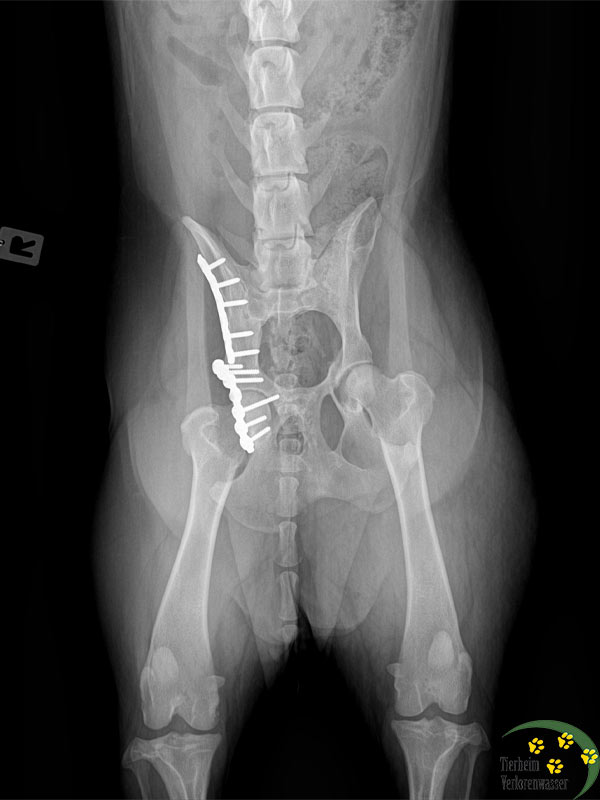

Beide hatten arge Gelenkprobleme. Deshalb fuhren wir zu einem spezialisierten Chirurgen nach Berlin. Bei Frieda musste der Tierarzt in einer komplizierten Operation die Platten entfernen, die früher einmal bei ihr eingesetzt worden waren. Es hatten sich Schrauben gelockert. Frieda konnte nicht mehr richtig laufen und litt große Schmerzen.

Die Voruntersuchungen und vorausgegangenen Maßnahmen kosteten schon über 1.000 €.

Für die Operationen kamen nun trotz eines saftigen Rabattes noch einmal 2.181,75 € hinzu.